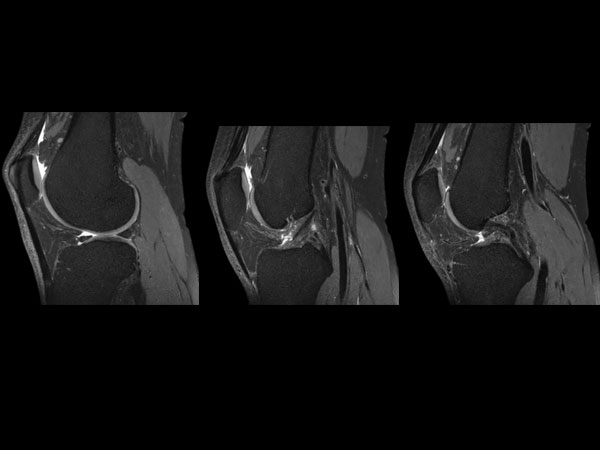

3D Knee imaging with MSK VIEW